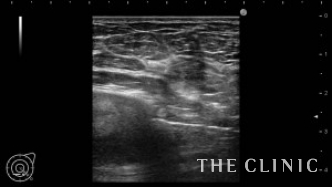

脂肪を崩して完全に吸引除去しました。